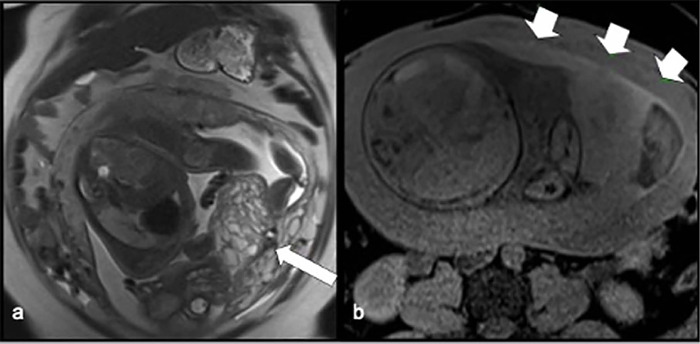

妊娠滋养细胞疾病(GTD)包括由双胎妊娠受精期间发生的遗传异常引起的异质性疾病,通常可能与辅助生殖技术有关。一种极其罕见的GTD的表现是双妊娠葡萄胎与胎儿共存,这种情况可能是母亲和胎儿并发症的重要原因。一名36岁的女性(G2, P0, A1)接受了友好的卵巢控制刺激(COS),然后进行了宫内人工授精(IUI)以辅助生殖为目的,导致双胎妊娠,最初的特征是两个妊娠囊。然而,一个囊未能发育,而是退化为磨牙滋养细胞疾病,而另一个则维持正常胎儿的正常生长。在妊娠33周时,患者出现先兆子痫,需要在三级医疗机构进行剖宫产。生殖辅助手术可能与滋养细胞疾病有关。此外,囊性病变的存在需要广泛的鉴别诊断,磁共振成像是准确评估和区分结构的有价值的工具。

Gestational trophoblastic diseases (GTD) comprise a heterogeneous group of disorders arising from genetic anomalies occurring during fertilization in twin pregnancies and often may be associated with assisted reproductive techniques. An exceedingly rare presentation of GTD is a twin pregnancy hydatidiform mole with a co-existing fetus, condition which may be an important cause of complications for the mother and the fetus. A 36-year-old woman (G2, P0, A1) underwent a friendly controlled ovarian stimulation (COS) followed by intrauterine insemination (IUI) for assisted reproductive purposes, resulting in a twin pregnancy initially characterized by two gestational sacs. However, one sac failed to progress and instead degenerated into molar trophoblastic disease, while the other sustained a normal fetus with regular growth. At 33 weeks gestation, the patient developed preeclampsia, necessitating delivery via cesarean section at a tertiary care facility. Reproductive-assisted procedures may be linked to cases of trophoblastic disease. Additionally, the presence of cystic lesions warrants a wide differential diagnosis, with magnetic resonance imaging serving as a valuable tool for accurate assessment and differentiation of structures.